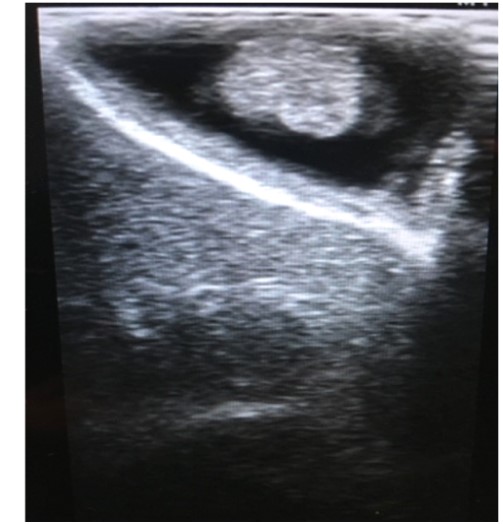

胆囊息肉的超声表现

B超:超声是检查胆囊息肉最便捷有效的检查方法,典型的胆囊息肉表现为胆囊壁向腔内凸起的高回声,后方无声影,不随体位改变移动。